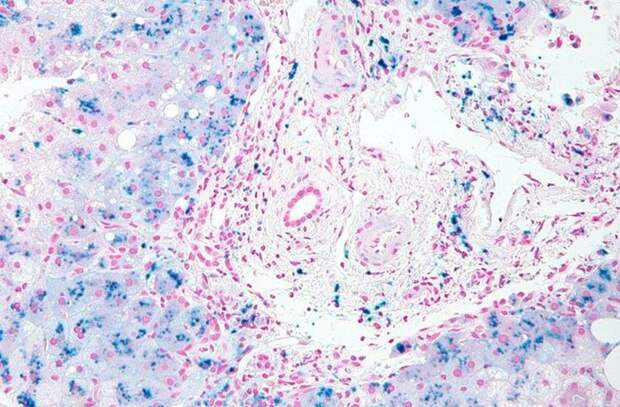

Гемохроматоз - это генетическое нарушение, которое приводит к чрезмерному накоплению железа в организме. «Перегрузка организма железом» настолько распространена в Ирландии, что стала известна как «кельтское проклятие». Генетический анализ показывает, что эта мутация была доставлена на остров в бронзовом века мужчиной, ДНК которого показало, что он был родом из понтийских степей. Исследователи сравнили генетику ирландской фермерши неолитического периода (которая умерла 5200 лет назад) и мужчины бронзового века мужчин, умершего 1200 лет спустя.

У темноглазой шатенки предки явно были охотниками-собирателями преимущественно ближневосточного происхождения. Люди бронзового века уже имели гены голубых глаз (наиболее распространенную Y-хромосому в современной Ирландии), были не настолько восприимчивы к лактозе и имели мутировавший ген C282Y, ведущий к «кельтскому проклятию». Сильная разница в генетике предполагает, что Ирландия столкнулась с периодом сильной миграции.